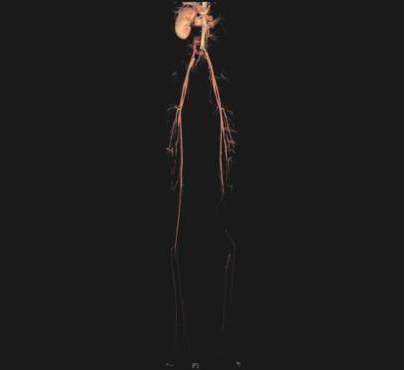

图一 心脏超声显示二尖瓣大量反流 图二 左侧腘动脉以下闭塞

入院时,洋洋被查出患有脑部栓塞,虽暂时还没有造成偏瘫等后遗症,但加上本身病程较长,如何将围手术期的风险降到最低成了当前最需要解决的问题。于是,由心脏外科牵头,联合血管外科、ICU、麻醉科的多位专家组成多学科讨论,对洋洋的手术方案、术中可能的风险及术后恢复等相关问题展开了探讨,最终决定此次手术先由心脏外科处理瓣膜问题,择期再由血管外科解决下肢栓塞的情况。